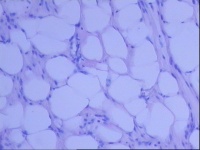

请教老师,子宫平滑肌瘤伴脂肪变性、钙化?还是脂肪瘤性平滑肌瘤?

发现子宫肌瘤2年余,行全子宫切除术

在子宫肌层肌壁间可见一大小约13.5*10*8CM的巨大瘤结节,挤压宫腔。瘤结节表面灰白、淡黄色,切面灰白、淡黄色,质软,与周围组织界限欠清。